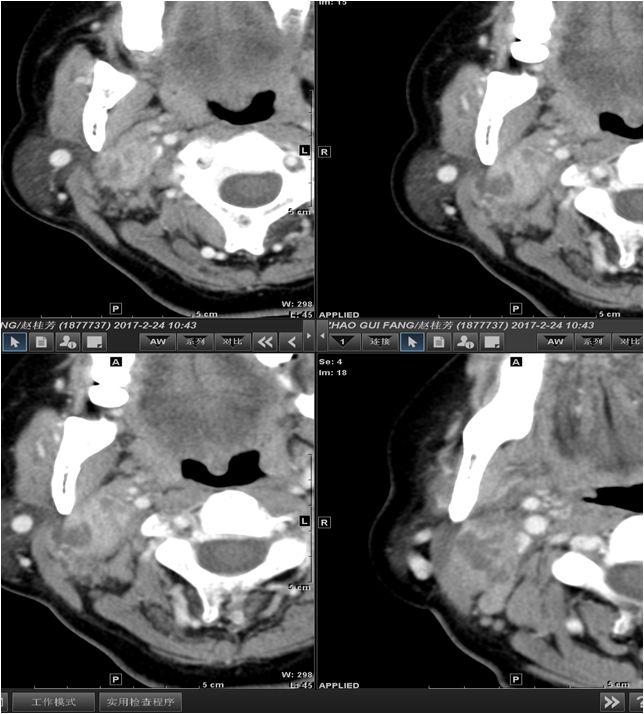

04 咀嚼肌间隙、颌下间隙、左侧颞下间隙,颊间隙,翼颌间隙

男,55岁,左下后牙反复肿疼1年余,加重1月余,疼痛剧烈伴张口受限,面部肿胀。

咀嚼肌间隙有脓肿形成。